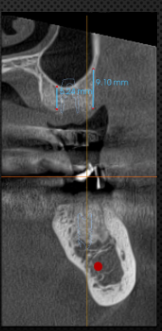

2mm safety zone from anatomical structures8mm long implant, 10 mm from IAN canal

Platform of implant: 2mm bellow the CEJ (3mm for ant teeth)